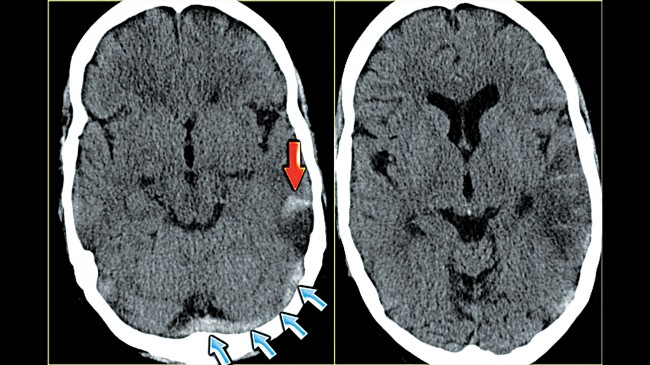

脳静脈血栓症を診断するとき、医師は通常、症状を評価し、病歴や家族歴を聞きます。最終的な診断は通常、脳内の血液循環をチェックすることで決まります。血流をチェックするために、医師は画像検査を使用して血栓や腫れを検出できます。

CVT の検出に使用される画像検査には次のものがあります。

• MRI 静脈造影検査: MRI静脈造影検査は、MRV とも呼ばれ、頭と首の領域の血管の画像を生成する画像検査です。血液循環、異常、脳卒中、脳出血の評価に役立ちます。このMRIでは、医師は特殊な色素を使用して血流を示し、血液が凝固しているかどうかを判断します。この検査は通常、CT スキャンの画像を鮮明にするために使用されます。

• CT 静脈造影: CTスキャンでは、X 線画像を使用して医師に骨と動脈血管を表示します。医師は静脈造影検査と組み合わせて、静脈に色素を注入して血液循環の画像を生成し、血液凝固の検出に役立てます。